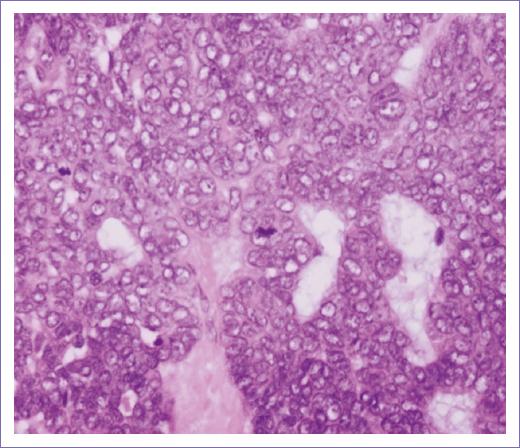

– Descripción microscópica. Los cortes histológicos examinados muestran la piel que presenta la epidermis sin alteraciones (Fig. 1); subyacente se observa tumor maligno de anexos cutáneos con patrón de crecimiento sólido, con proliferación de células de aspecto basaloide con núcleos vesiculosos. Pleomorfismo moderado y un índice mitósico de 4xCSF (40x) (Fig. 2). La neoplasia presenta formación de lúmenes intracitoplásmicos multifocales (Fig. 3). Los bordes del tumor son infiltrativos a nivel de dermis reticular (Fig. 4). No se identifica permeación vascular linfática. El lecho quirúrgico y bordes quirúrgicos no presentan lesión neoplásica.

Figura 1 Resección de neoformación de mejilla (magnificación 4x). Neoplasia sólida de epitelio de glándula sudorípara de bordes empujantes.